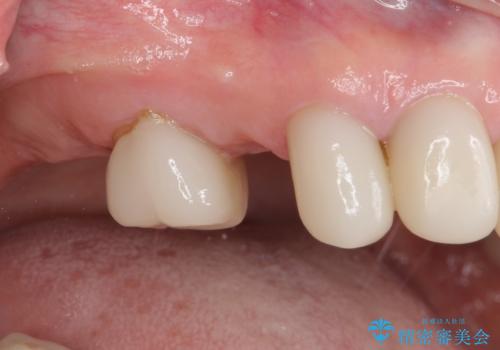

- 虫歯や歯の欠損を放置していることを気にして来院された患者様です。

下顎には抜歯が必要な歯があったため、抜歯後に治癒を待ち、上顎とともにオールセラミックブリッジにて補綴治療を行うこととしました。

治療開始の日に欠損部も含めて仮歯が装着され、今までの不具合や不快感があっという間に改善されました。

抜歯部位の治癒を待つために時間がかかりましたが、来院回数は数回で済み、患者様には大変満足していただきました。